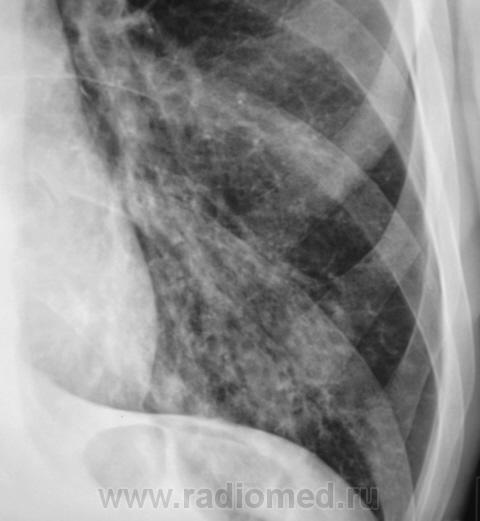

Пациент направлен на рентгенографию ОГК с диагнозом - "Левостороняя пневмония".

Анамнез стандартный. Ранее неоднократно страдал обострениями хронического бронхита. Сейчас вот не нашутку занемог - температура до 38, откашливает мокроту, кашель продуктивный.

Диагноз левосторонней нижнедолевой С10, С9 сементарной пневмонии наверное будет верным, а с учётом фона- с наличием бронхоэктазов.